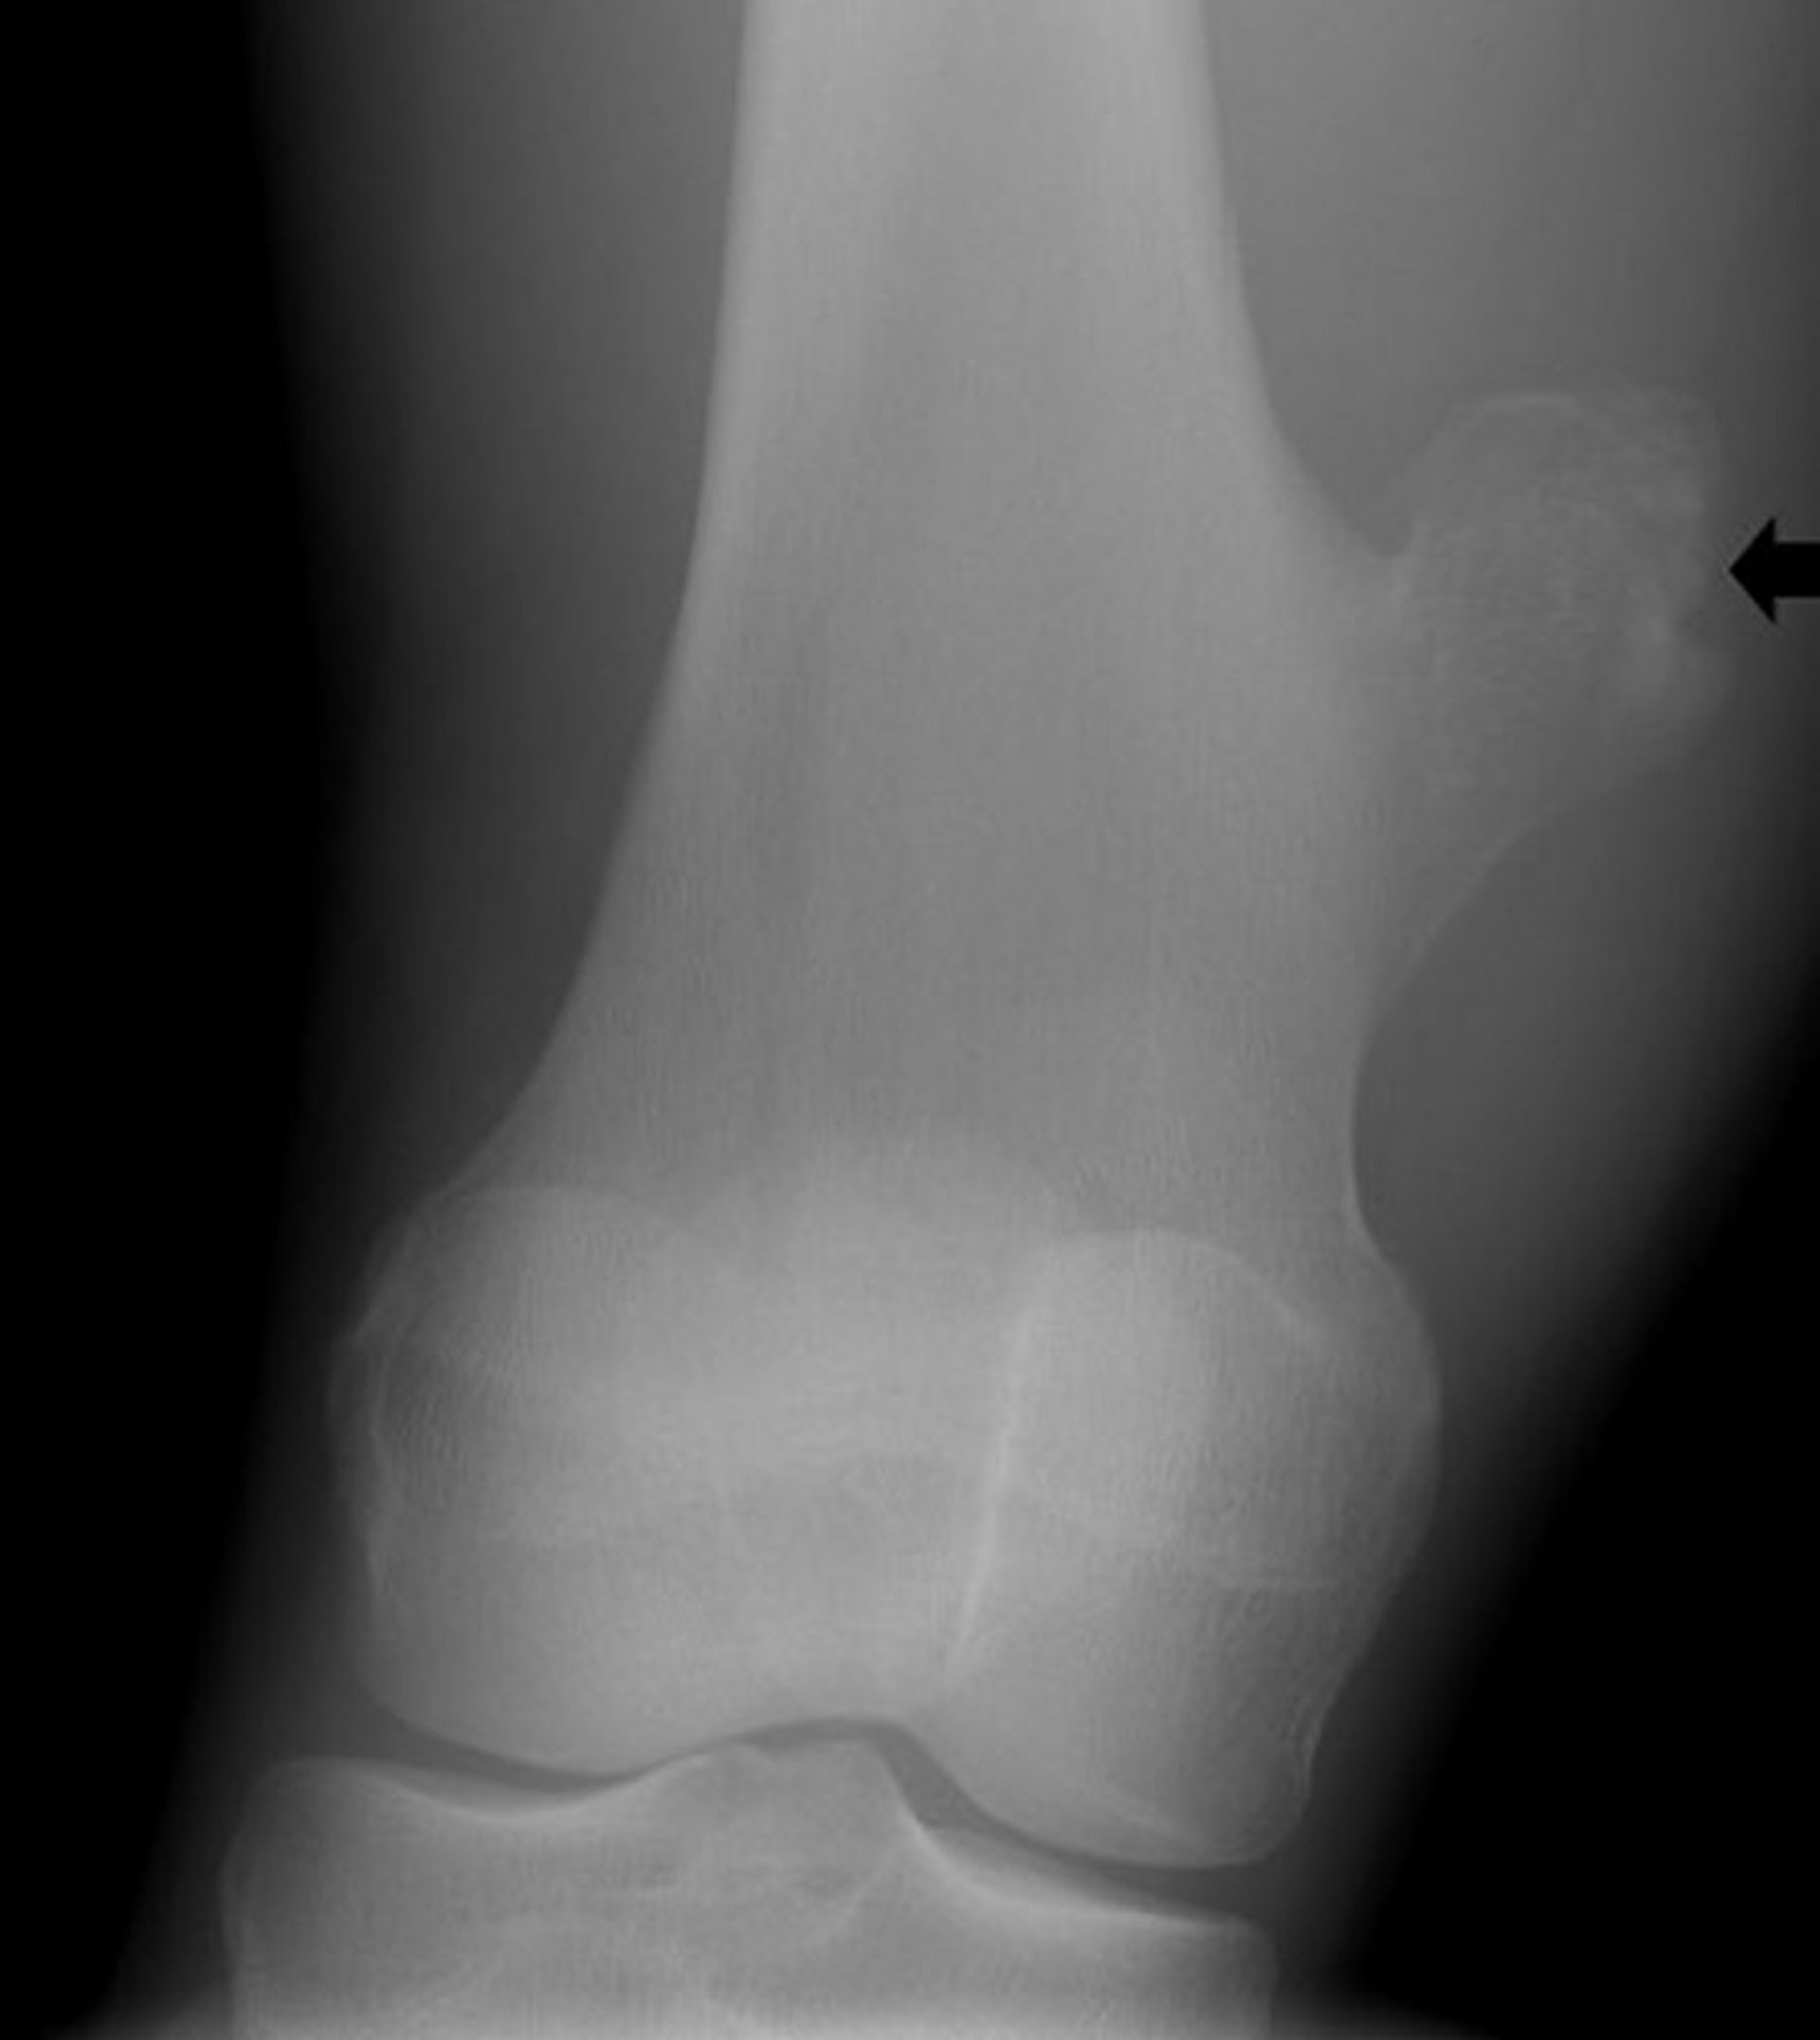

Osteochondrom des Knies

Diese Röntgenaufnahme des Knies zeigt einen knöchernen Auswuchs (Pfeil) vom Femur oberhalb des Kniegelenks, das mit einem Osteochondrom übereinstimmt.

Image courtesy of Michael J. Joyce, MD, and Hakan Ilaslan, MD.